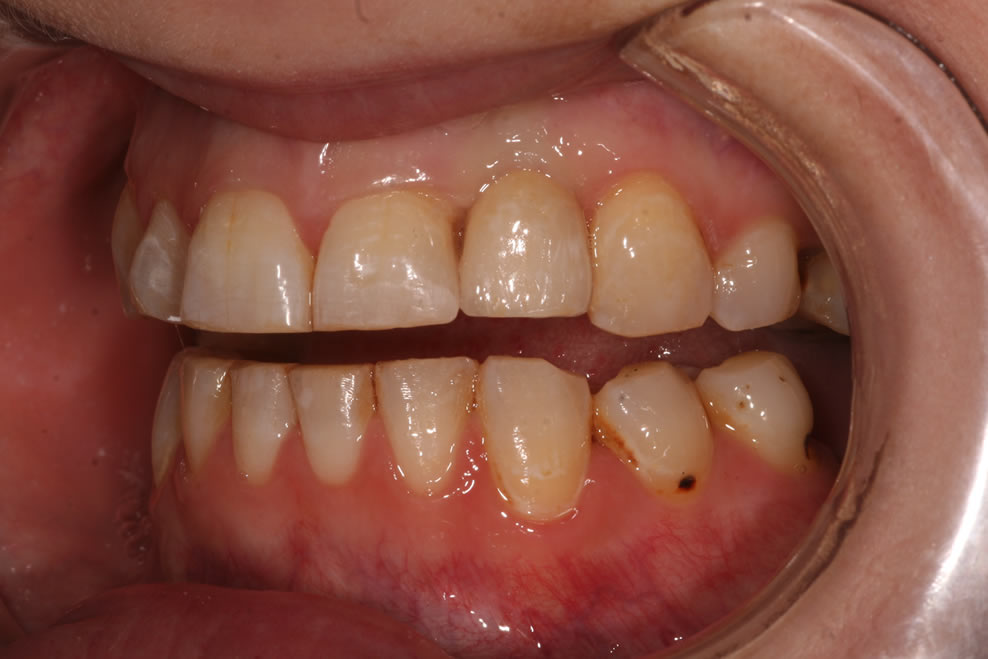

Dental implants are the best-known treatment to replace single or multiple missing teeth because they feel and behave just like natural teeth. After a while you won’t be able to tell the difference – even forgetting that they are there.

The procedure to place implants and replace a missing tooth or multiple teeth is straightforward as there is little need to treat surrounding teeth. Once a crown is placed over the implant it will appear indistinguishable from the natural teeth.

GIVING ANNETTE MORE CONFIDENCE WITH

DENTAL IMPLANTS